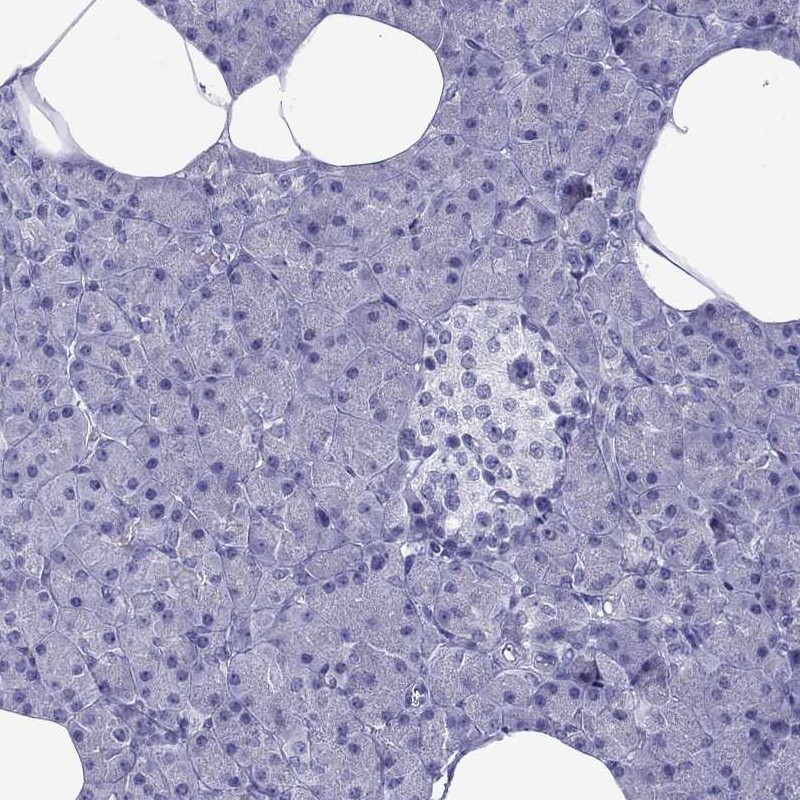

Immunohistochemistry analysis in human heart muscle and pancreas tissues using Anti-MYLK3 antibody. Corresponding MYLK3 RNA-seq data are presented for the same tissues.